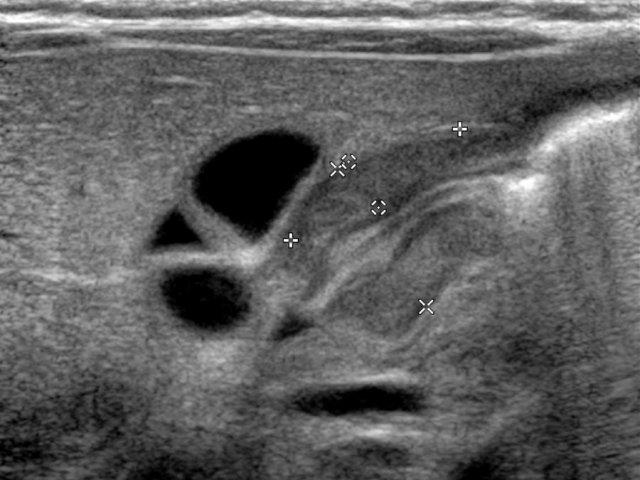

Siêu âm ở trẻ nhịn ăn sẽ cho thấy dịch ứ đọng trong dạ dày. Không có sự lưu thông qua cơ môn vị phì đại.

Đường kính ngang của thành cơ đơn là số đo đáng tin cậy nhất để chẩn đoán phì đại cơ môn vị.

Số đo lớn hơn 3 mm trên hình cắt ngang cho thấy phì đại cơ.

Đường kính ngang toàn bộ lớn hơn 14 mm và chiều dài toàn bộ ống môn vị lớn hơn 15 mm hỗ trợ cho chẩn đoán.

- Thành cơ đơn > 3mm

- Đường kính ngang toàn bộ > 14mm

- Chiều dài ống môn vị > 15mm